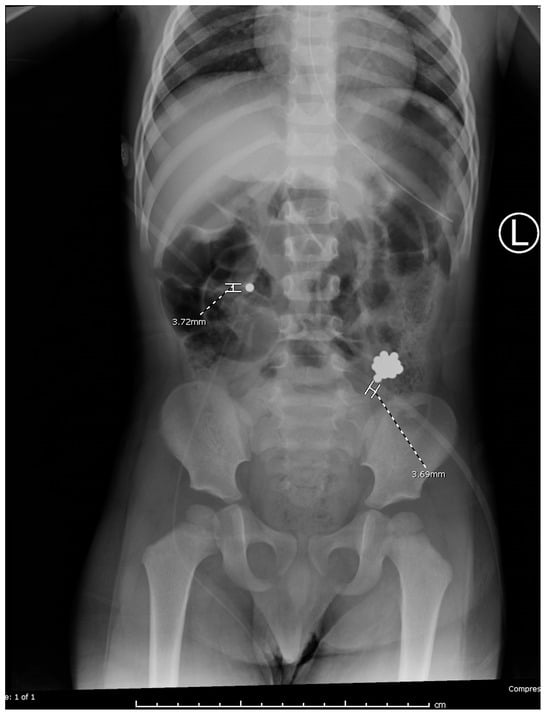

Interventions occurred across multiple anesthetic settings. Otolaryngology performed direct laryngoscopy, successfully removing two magnets adhered to the uvula with minimal trauma, consistent with findings from previous studies [4]. Gastroenterology then conducted an upper endoscopy, revealing a tightly clustered arch of 30 bb-sized magnets compressing the gastric incisura (Figure 2). Using a Roth net, they removed the magnets in two passes with no complications other than minor erosions on the gastric mucosa. Post-procedural imaging revealed residual magnets in the proximal jejunum (Figure 3).

Figure 2. A cluster of 30 bb-sized magnets was retrieved using a roth net in two passes. Superficial bb-sized erosions were noted on the proximal incisura.

Figure 3. Post-op abdominal radiographs revealed multiple magnets remaining in the proximal jejunum.